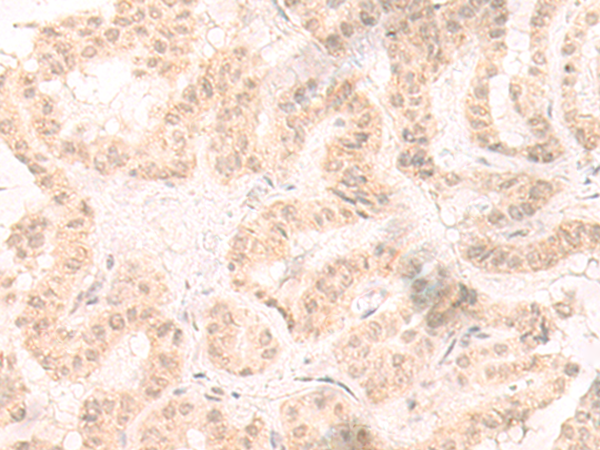

分类: 科研抗体货号: P06447别名: IL-7应用: WB,IHC反应种属: Human, Mouse